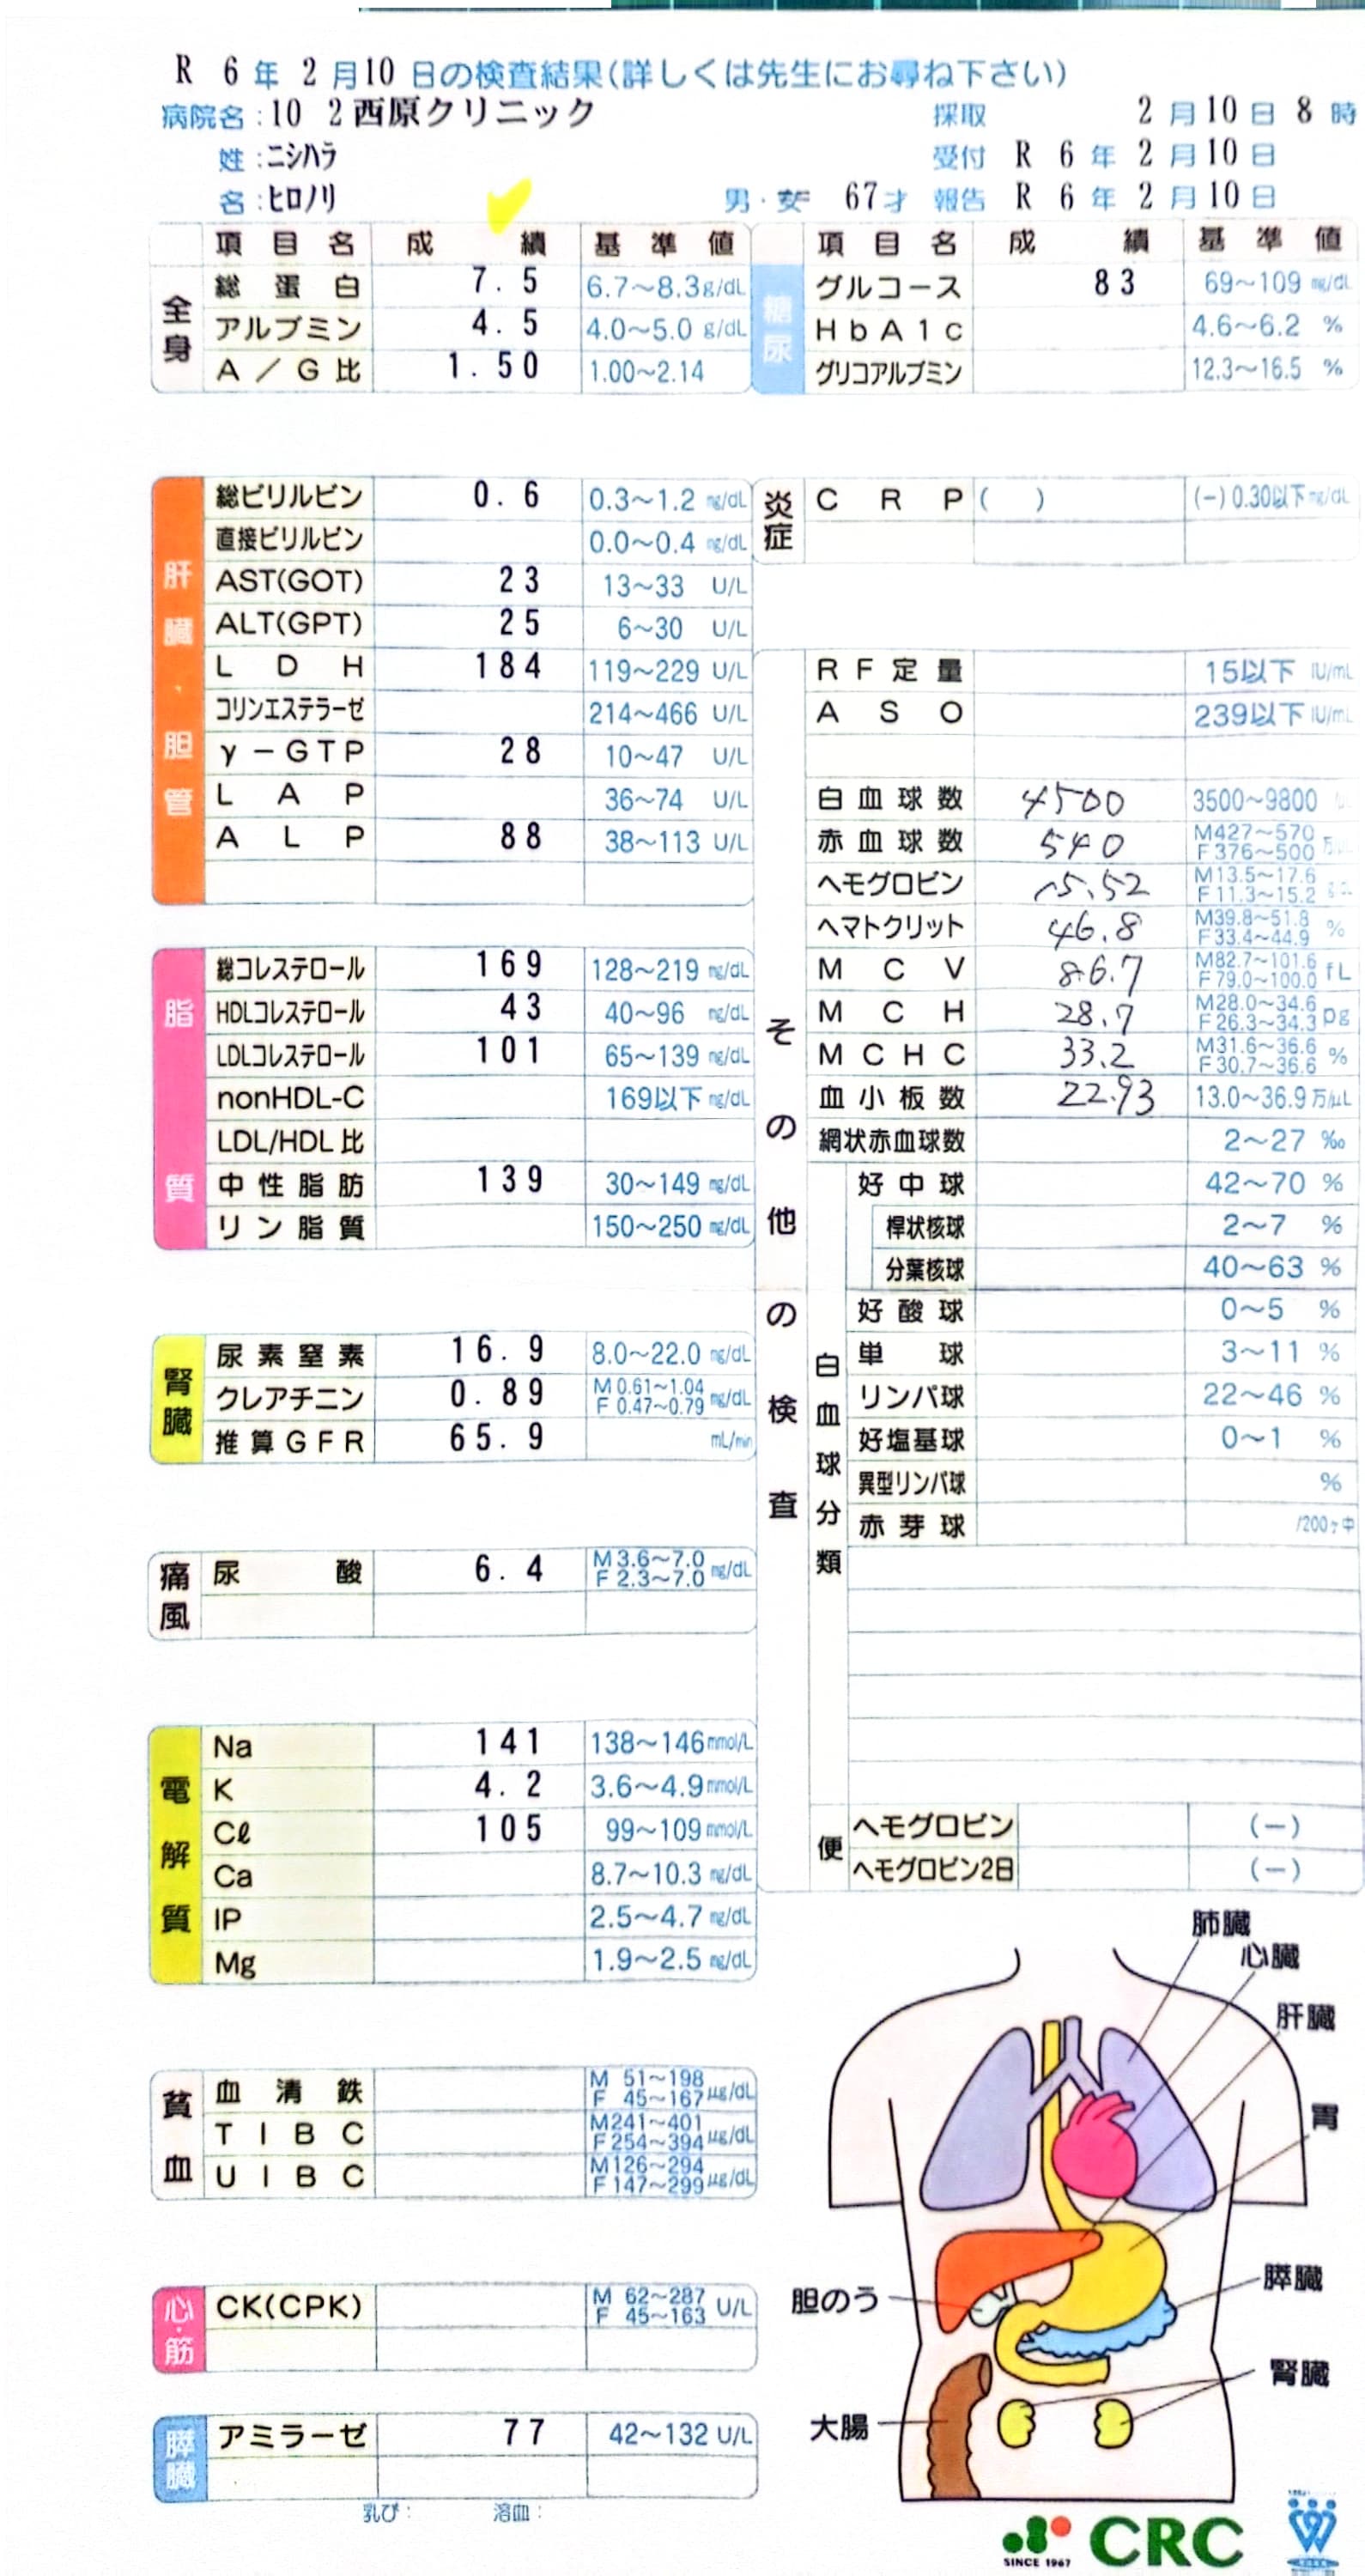

2024.3.9 鼻炎と目のかゆみがひどく、オロパタジン⇒デザレックス&点眼薬 アレジオン に変更 2.10 血液検査結果